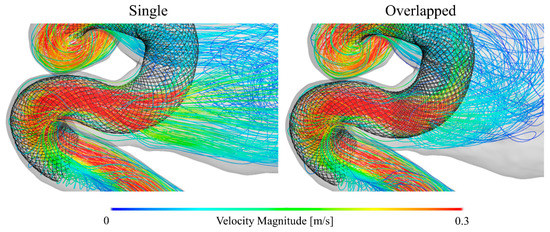

What does CFD stand for in Biomedical Engineering. CFD is the science of predicting fluid behaviour Flow field heat transfer mass transfer chemical reactions etc By solving the governing equations of fluid flow using a numerical approach computer based simulation The results of CFD analyses Represent valid engineering data that may be used for. Structured multi-block grid for an unruptured aneurysm in a cerebral artery a test case used in CFD Rupture Challenge 2013.

Search for PhD funding scholarships studentships in the UK Europe and around the world. CFD is capable of providing valuable hemodynamics which is useful in the clinical assessment of heart performance and the early diagnosis of heart dysfunction 3 6 7. The review then focuses on the applications of CFD in biomedical problems including cardiovascular diseases airflow pattern and aerosol deposition in lungs cerebrospinal fluid flow in brain and for artificial organ design analysis.